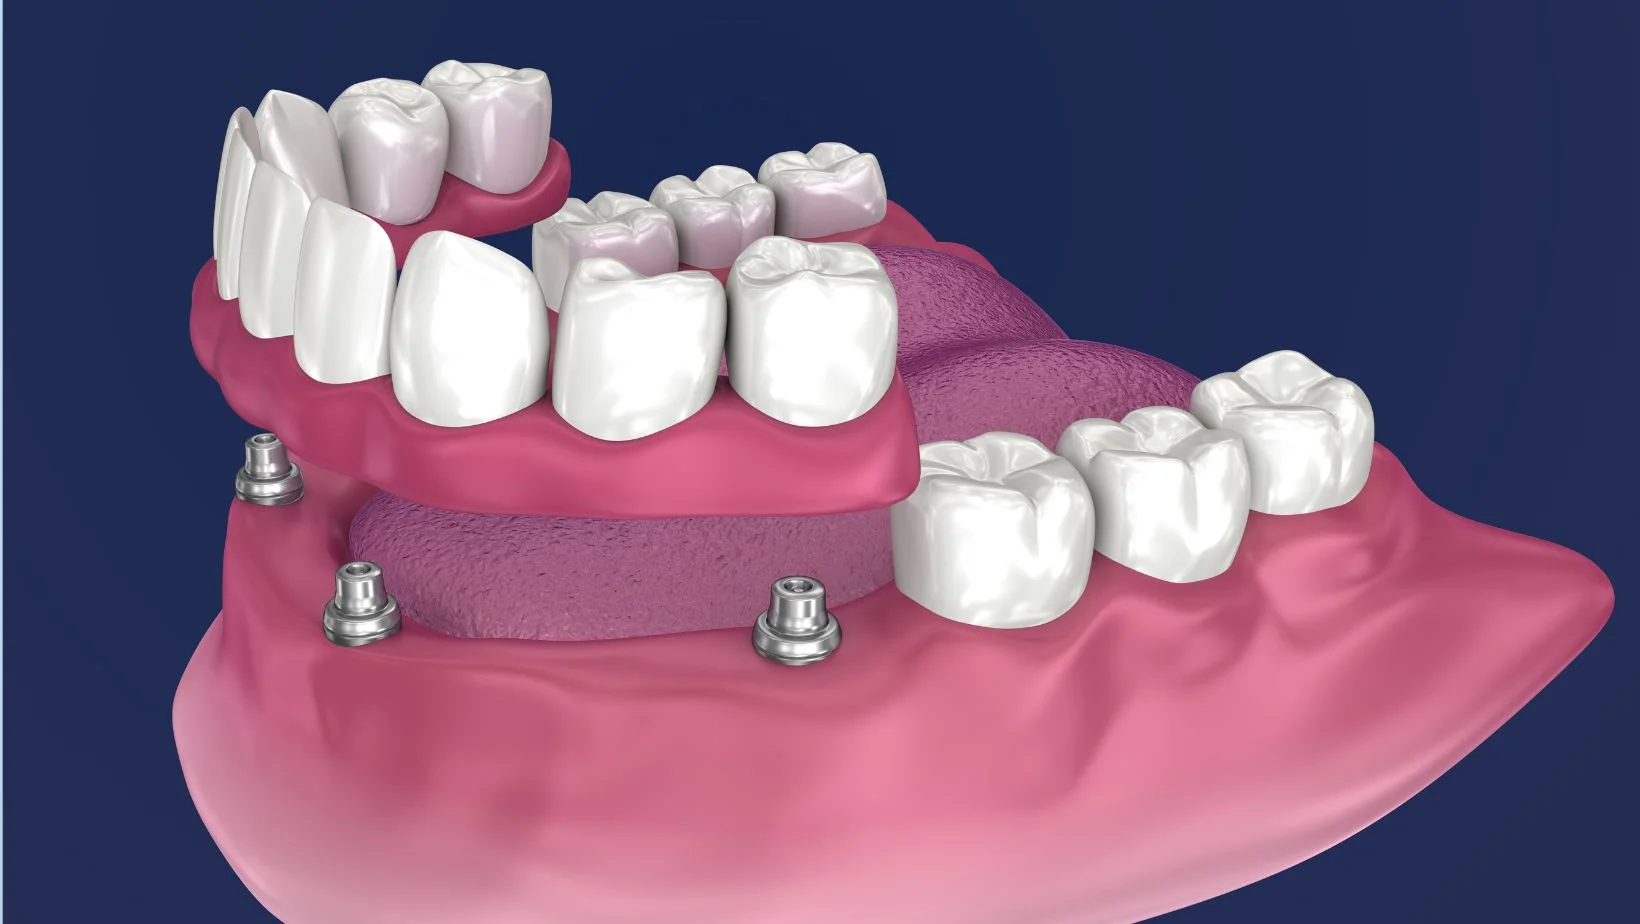

Removible con locators (mucha retención, fácil higiene).

Fija total (arcada completa) atornillada a implantes.

Arcada inferior con alta retención y comodidad, removible para higiene diaria. Gran mejora de estabilidad.